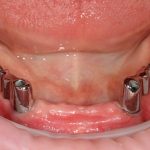

Имплантационная система и необходимые материалы:

Для решения поставленной клинической задачи мы выбрали имплантационную систему Xive. Из имеющихся у нас трёх имплантационных систем, она лучше всего подходит для немедленной имплантации и немедленной нагрузки, и вот, почему:

Теоретически, для данной работы мы можем использовать абсолютно любую имплантационную систему, но с Xive это сделать проще. Тем более, что в клинике мы держим склад из более, чем трехсот имплантатов и компонентов, поэтому не переживаем по поводу того, что к моменту операции чего-то не будет в наличии. У нас всё всегда есть.

Прежде, чем приступить к аугментации (пластике) лунок зубов, мы подготовили лунки для имплантатов. В таких клинических случаях нет необходимости в использовании шаблона. Вместо этого, мы применяем общепринятые правила позиционирования и соблюдаем рекомендации производителя по хирургическому протоколу:

В процессе ирригации лунки промываются, что позволило нам еще раз подтвердить ранее сделанные выводы. С помощью аналогов имплантатов, входящих в хирургический набор Xive, мы проверили возможность стабилизации имплантатов в будущих лунках. Исходя из правил подбора и позиционирования имплантатов (я очень рекомендую почитать об этом здесь>>) мы остановились на Xive S диаметром 3,4 мм и длиной 13 мм.